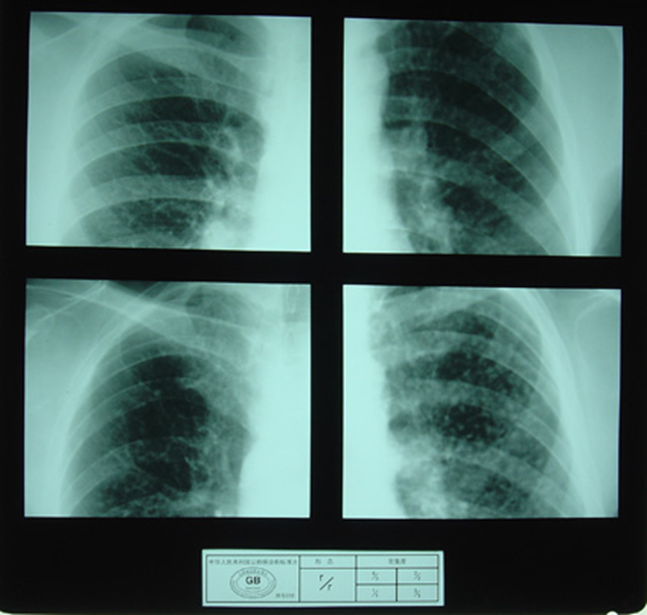

(2)X射线胸片表现:矽肺X射线胸片影像是肺组织矽肺病理形态在X射线胸片的反映,是“形”和“影”的关系,与肺内粉尘蓄积、肺组织纤维化的病变程度有一定相关关系,但由于多种原因的影响,并非完全一致。这种X射线胸片改变表现为X射线通过病变组织和正常组织对X射线吸收率的变化,呈现发“白”的圆形或不规则形小阴影,作为矽肺诊断依据。X射线胸片上其他影像,如肺门变化、肺气肿、肺纹理和胸膜变化,对矽肺诊断也有参考价值。在X射线胸片上,肺野内直径或宽度不超过10mm的阴影。小阴影按其形成分为圆形和不规则形两类。

1)圆形小阴影:是矽肺最常见和最重要的一种X线表现形态,其病理基础以结节型矽肺为主,呈圆或近似圆形,边缘整齐或不整齐,直径小于10mm,按直径大小分为p(<1.5mm)、q(1.5~3.0mm)、r(3.0~10mm)三种类型。p类小阴影主要是不太成熟的矽结节或非结节性纤维化灶的影像,q、r类小阴影主要是成熟和较成熟的矽结节,或为若干个小矽结节的影像重叠。圆形小阴影早期多分布在两肺中下区,随病变进展,数量增多,直径增大,密集度增加,波及两上肺区。

圆形小阴影(p类小阴影)

圆形小阴影(q类小阴影)

圆形小阴影(r类小阴影)

观察对象

尘肺壹期

尘肺贰期

尘肺壹期